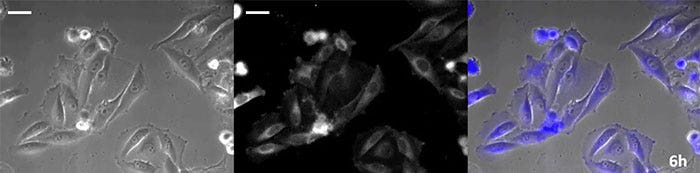

La luciferina de tipo coelenteracina posee un brillo especialmente alto; no obstante, su oxidación en la célula tras un corto período de tiempo conlleva a que sea agregada adecuadamente, lo que es esencial en las aplicaciones de observación a largo plazo. Para dar solución a este problema, se ejecutó la perfusión de células con una proteína luminiscente de alta intensidad, al mismo tiempo que un dispositivo de adición de sustrato automatizado agregó automáticamente la coelenterazina para que la luminiscencia pudiera ser monitoreada continuamente. Como resultado, se logró monitorizar la imagen luminiscente en combinación con el procesamiento de imágenes de contraste de fase durante más de 24 horas (Figura 4).

0 horas

Figura 4-1 0 horas

6 horas

Figura 4-2 6 horas